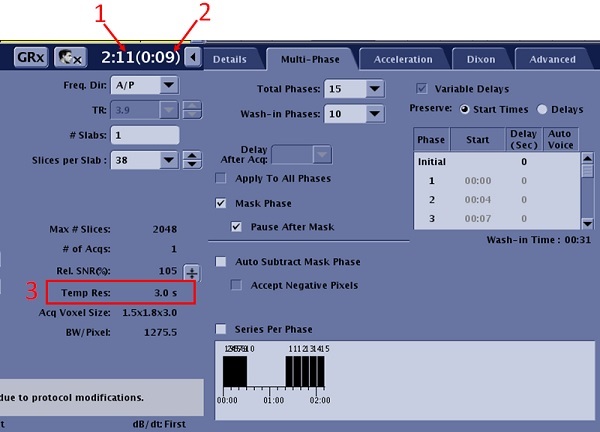

- Click the Multi-phase tab and make adjustments as needed.

Figure 4. Detail and Multi-phase tabs with DISCO: Variable Delay

Table 1. Image legend Number Description of Detail tab 1 Total time excluding Mask. 2 Duration for Mask or non-wash-in phases. 3 Temporal resolution for wash-in phases. Table 2. Multi-Phase tab selections Selection Description Total Phases

- The Total Phases does not include the mask phase.

- For a prostate exam, enter the number of phases required to adequately capture the contrast wash-out, approximately 6 minutes.

- For a breast exam, enter the number of phases required to adequately capture the contrast wash-out, approximately 10 minutes.

Wash-in Phases

- The number of phases from the time of injection to the completion of contrast uptake in the area of interest.

- For a liver exam, enter the number of wash-in phases that will fit within a breath-hold

Variable Delays

- Variable Delays is forced On for DISCO.

- When Smart Prep is selected with Multi-Phase and Variable Delays, the Image Acquisition Delay User CV and the first phase delay have the same value. If either value is changed, the other value is automatically adjusted.

- Preserve options determine if the start time is kept or the delay time is kept for each phase when the scan time is changed.

- Initial represents the delay time that occurs before the first phase and after the mask phase. The time delay is the time from clicking Scan to the start of the acquisition of the first phase, post mask. Screen contents and ability to edit the values in the table varies, based on other Multi-phase tab selections.

- The mask phase is not represented in the Variable Delay display and is not included in the Total Time. You can change the delay time for the initial phase and it will not change the Total Time. Change the delay time for any of the other phases and the Total Time updates.

- Each time you enter a phase delay, the system recomputes and updates the corresponding and subsequent phase start times.